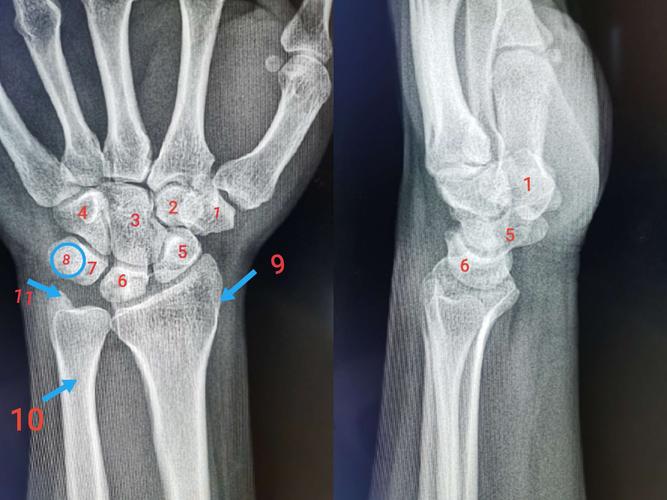

小多角骨 3.头状骨 4.勾状骨 5.舟状骨 6.月状骨 7.三角骨 8.

医药卫生 临床医学 腕舟骨骨折ppt 近侧列依次为手舟骨,月骨,三角骨